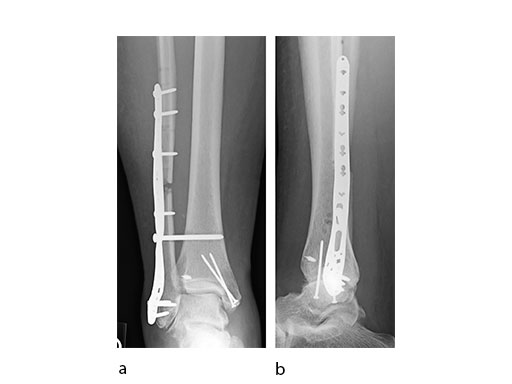

A 45-year-old patient fell from his horse, receiving a closed bimalleolar fracture/ dislocation (Fig 10). Computed tomorgraphy demonstrated an additional anterolateral avulsion injury and syndesmosis dislocation. Osteosynthesis was conducted with a VA-LCP Lateral Distal Fibula Plate.

Push technique was required to achieve fibular reduction, and the syndesmosis was reduced and clamped with periarticular clamps (Fig 11). Postoperative x-rays at 4 weeks demonstrated good maintenance of reduction (Fig 12).